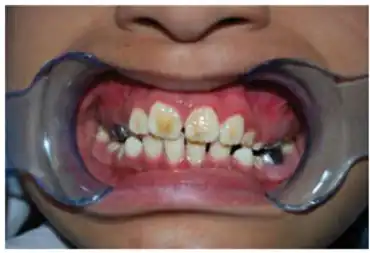

There are some physical symptoms that have been associated with KTS. The most prominent symptom is amelogenesis imperfecta which gives the teeth a stained brown-yellow color. The enamel is thin, rough, and prone to crumbling. Two types of amelogenesis imperfecta (AI) have been seen in KTS patients. The first is Hypoplastic which is caused by the enamel being underdeveloped, and the second is hypo-calcified which causes the enamel to be soft and chalky. AI originated as a heterogeneous syndrome but has been observed as homogeneous in the case of KTS.[5][6][10] Other physical symptoms that some cases have presented with include broad thumbs and toes, microcephaly, coarse hair, mildly asymmetric skull, up slanting palpebral fissures which is where the outside corners of the eyes are higher than normal, and smooth philtrum which is where the upper lip does not have a dip in the center.[5][10]